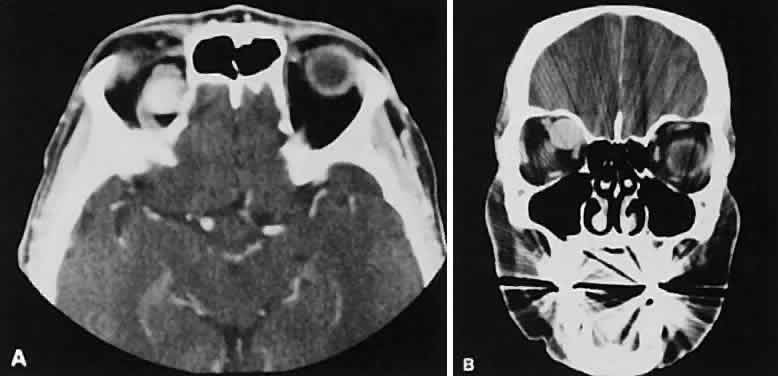

Malignant lesions of the lacrimal gland, conversely, often appear invasive, with bone destruction evident on the CT scan (Fig. 17). Intralesional calcium may be present.63,64 The use of contrast material facilitates detection of lesions that extend beyond the confines of the orbit.

Fig. 17. Adenocarcinoma of the lacrimal gland. A. Unenhanced axial view shows the speckled calcification of a lacrimal gland tumor. B. Contrast-enhanced view at about the same level shows intense enhancement and vascularity. In axial views at a higher level, an unenhanced scan (C) is unremarkable, although a contrast-enhanced view (D) at the same level highlights intracranial extension (arrows). E. Reconstructed coronal view has bone destruction with extension into the intracranial and temporalis fossae.